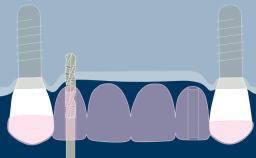

O planejamento de implante determinado por prótese garante que a instalação do implante seja compatível com o resultado final desejado, que é um fator-chave para resultados bem-sucedidos na terapia de implante. As tecnologias digitais agora disponíveis no campo da implantodontia facilitam o planejamento de implantes dirigidas por prótese dentária. Os benefícios dessas tecnologias incluem melhorias significativas na avaliação do paciente e no planejamento do tratamento, permitindo que os clínicos posicionem os implantes de suporte com um alto grau de precisão. Este Módulo de Aprendizado discutirá o uso rotineiro do planejamento baseado em computador para a instalação de implantes.